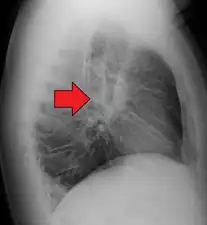

- Hilar adenopathy especially on the person's left (AP CXR)

- Hilar adenopathy especially on the person's left (lateral CXR)